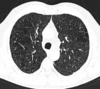

12

Q

A

Consolidación alveolar

How well did you know this?